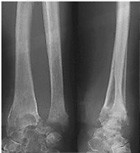

Spiral Fracture Tibia